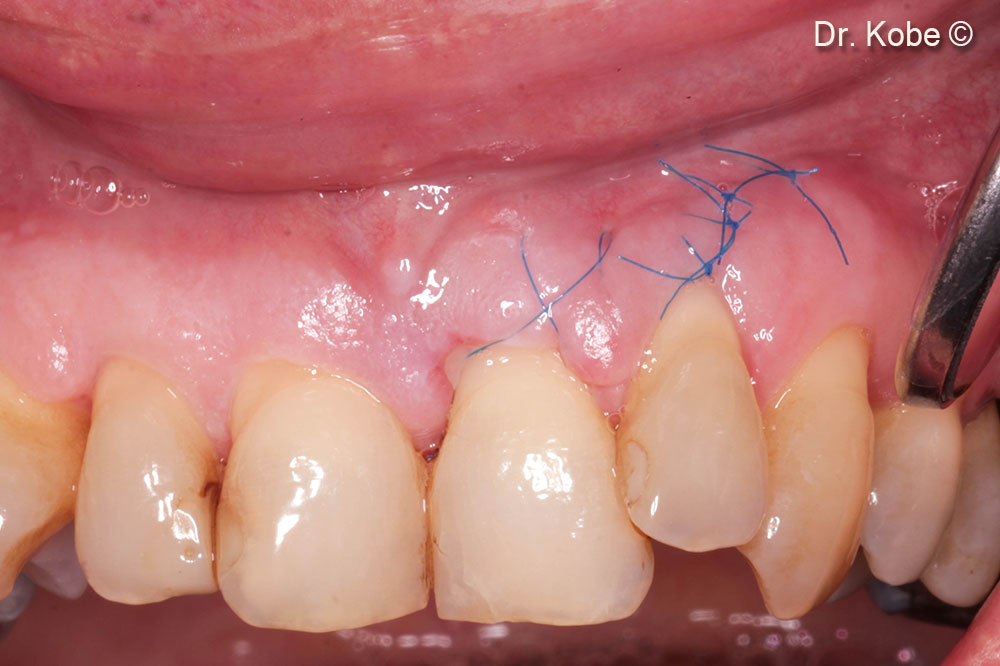

Khâu vết thương bằng vết khâu đơn giản gián đoạn

Theo dõi 1 tuần